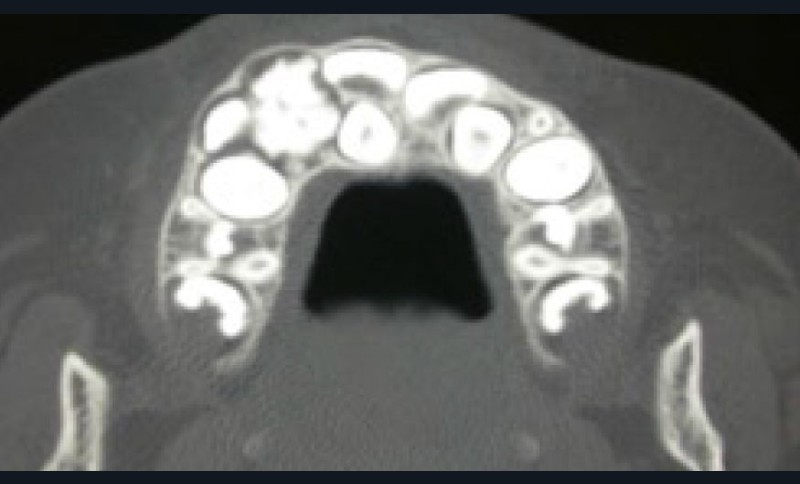

– l’odontome composé, correspondant à une masse dont l’anatomie ressemble à une dent ou à un ensemble de petites dents rudimentaires assemblées en amas, le plus souvent dans la région antérieure du maxillaire ;

– l’odontome complexe, décrit comme une masse anarchique de matériaux dentaire, retrouvé plus fréquemment dans les régions molaires, prémolaires.